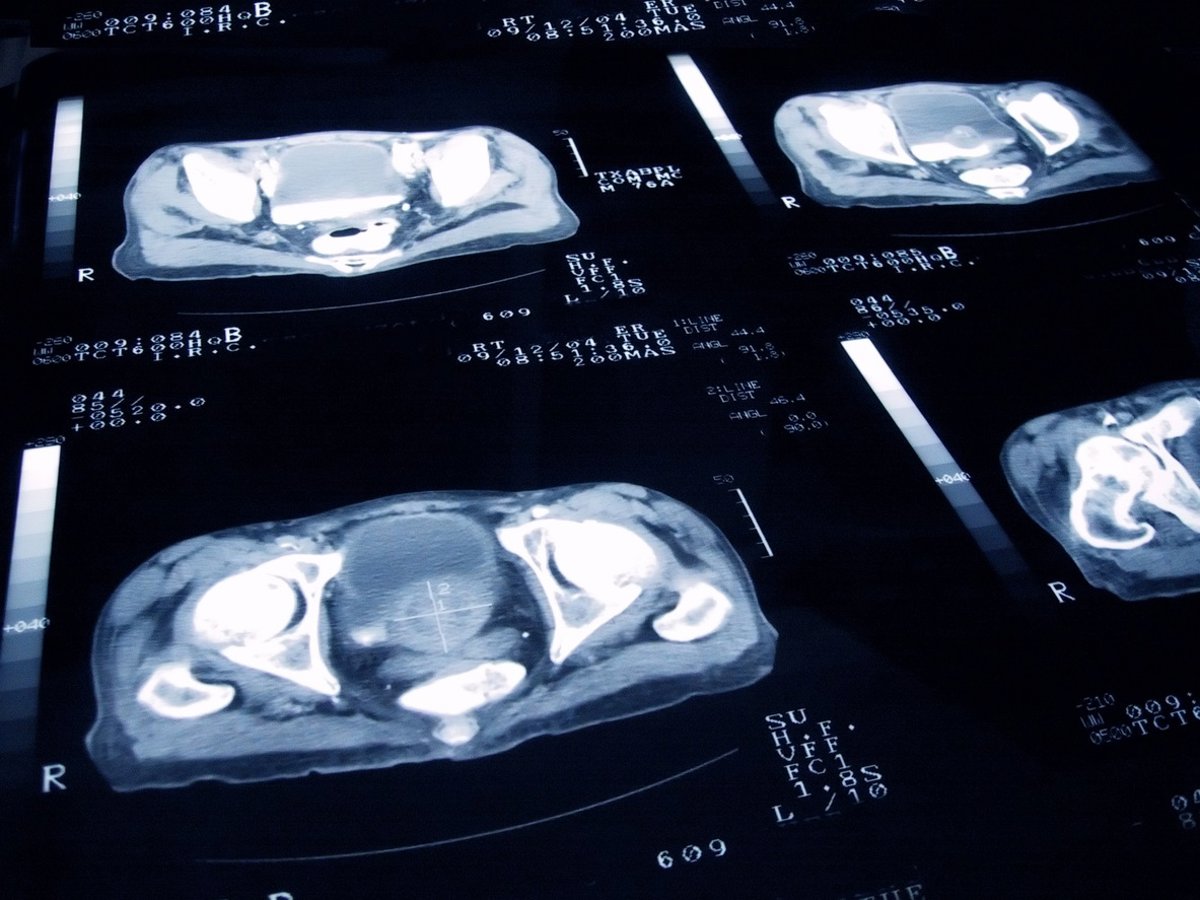

Archivo - Cáncer de próstata

Archivo - Cáncer de próstata - JAMESBENET/ ISTOCK - Archivo

La compañía biotecnológica Quibim ha presentado una de sus últimas innovaciones en el diagnóstico precoz de cáncer de próstata con Inteligencia Artificial (IA), denominada QP-Prostate, que es capaz de detectar un 10,6 por ciento más de casos en etapas iniciales, en el marco de la Reunión Anual de la Sociedad Radiológica de Norteamérica (RSNA), celebrada en Chicago (Estados Unidos).

Su última versión aporta "un nuevo nivel de inteligencia e interactividad a la imagen de la próstata", al incluir herramientas avanzadas de visualización y edición 3D que permiten a radiólogos y urólogos explorar la anatomía y las lesiones de la próstata con "mayor detalle", lo que facilita tanto la planificación como la selección de la biopsia.